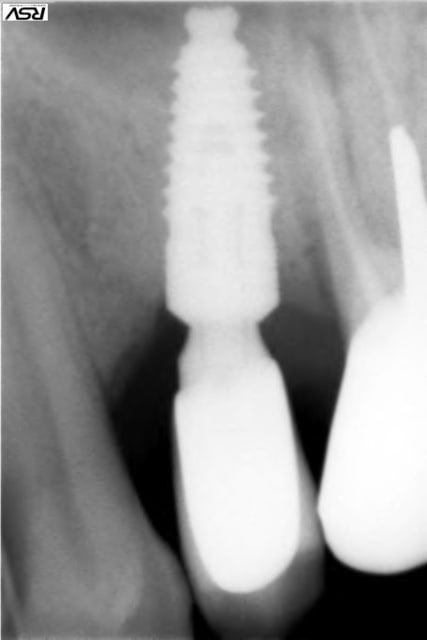

Tiens jette un coup d'oeil sur la partie mésial de cet implant sans comblement où 3 spires ont été englouties dans la cicatrisation osseuse

1 mrz3ip - Eugenol

2 ubljjt - Eugenol

> Tiens jette un coup d'oeil sur la partie mésial de cet implant sans comblement

> où 3 spires ont été englouties dans la cicatrisation osseuse

3 spires, cool, mais il en reste quelques une ?